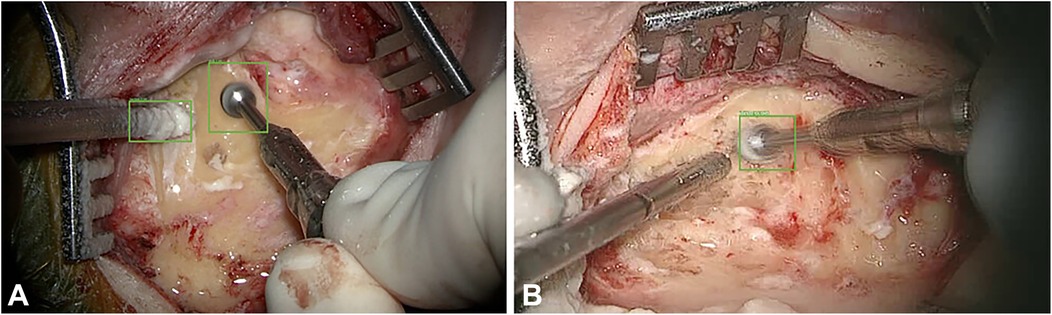

4.4 Applications of ML and hand and instrument tracking in neurosurgery

AI and ML have been applied to neurosurgery in several ways. Deep learning approaches have allowed neurosurgeons to track the movements of instruments intraoperatively. For example, in a paper by Raymond et al., a deep learning network was initially trained with images from surgery to recognize and track surgical instruments. The Residual Network 101, a CNN consisting of 101 deep layers, was used. These types of networks work by deconstructing aspects of the image and analyzing the different spectral bands in the image, allowing the network to identify specific components within the image. From here, the images were deconstructed in both low and high levels of resolution, eventually allowing for every detail of the image to be identified. This process is crucial for properly identifying surgical instruments within a video. After the deconstruction of these images, they were analyzed by a region proposal network, which allows for determining regions of interest. Once regions of interest have been identified, they are tested by the CNN to determine the accuracy of instrument recognition and prediction accuracy. Bounding boxes are used as a pictographic representation of these predictions. A computer vision model was used to track instruments during mastoidectomy surgeries. These deep learning technologies allowed the authors to track the exact coordinates of the surgical instruments during the procedure. Images from the procedure were analyzed as described above to determine the precise coordinates of these instruments and the bounding boxes. The model then measured outcomes such as the intersection over union ratio, accuracy, precision, and average precision (Figure 11) (83).

Figure 11. Machine learning (ML) applications in neurosurgery. Raymond et al. (83) tried to develop a convolutional neural network–based computer vision model to track 2 surgical instruments used in mastoidectomy procedures (drill and suction irrigator). Intraoperative video recordings were used to teach the model. Then, the model measured the outcomes, such as accuracy, precision, and average precision. The study stated 2 extremes regarding detection accuracy. (A) Detection accuracy for both the drill and the suction-irrigator was 100%. (B) Detection accuracy for the drill was 98%, but absent for the suction irrigator. Green bounding boxes were generated by the ML model to enhance visualization. Used with permission from Raymond MJ, Biswal B, Pipaliya RM, Rowley MA, Meyer TA. Convolutional neural network-based deep learning engine for mastoidectomy instrument recognition and movement tracking. Otolaryngol Head Neck Surg. 2024;170(6):1555–60. doi: 10.1002/ohn.733.